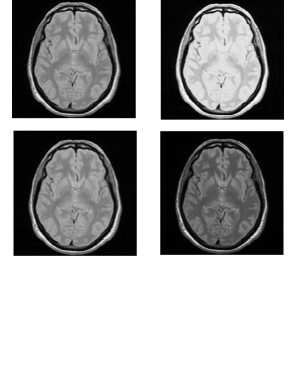

3.1.2. Adding known levels of non-standardness

We combine eight different ranges of the slopes and to introduce small, medium, and large scale non-standardness into the scenes. This means that, for each clean scene, we obtain eight scenes, one of which is the default clean scene itself, two scenes consisting of small scale non-standardness, two scenes consisting of medium scale non-standardness, and three scenes consisting of large scale non-standardness. The ranges of applied non-standardness are given in Table 1. We have arrived at these values by examining the training part of the standardization process through computing the ranges of the slopes and that are utilized in standardizing the corrected scenes. Figures 4 and 5 illustrate the process of introducing known levels of non-standardness into the clean slices of a PD and a T2-weighted scene utilized in our study. In both figures, the first display shows the original clean slice and the rest show the resulting non-standard slices.

![]() |